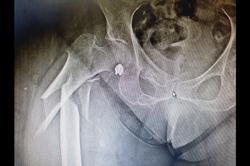

Neck Femur Fracture